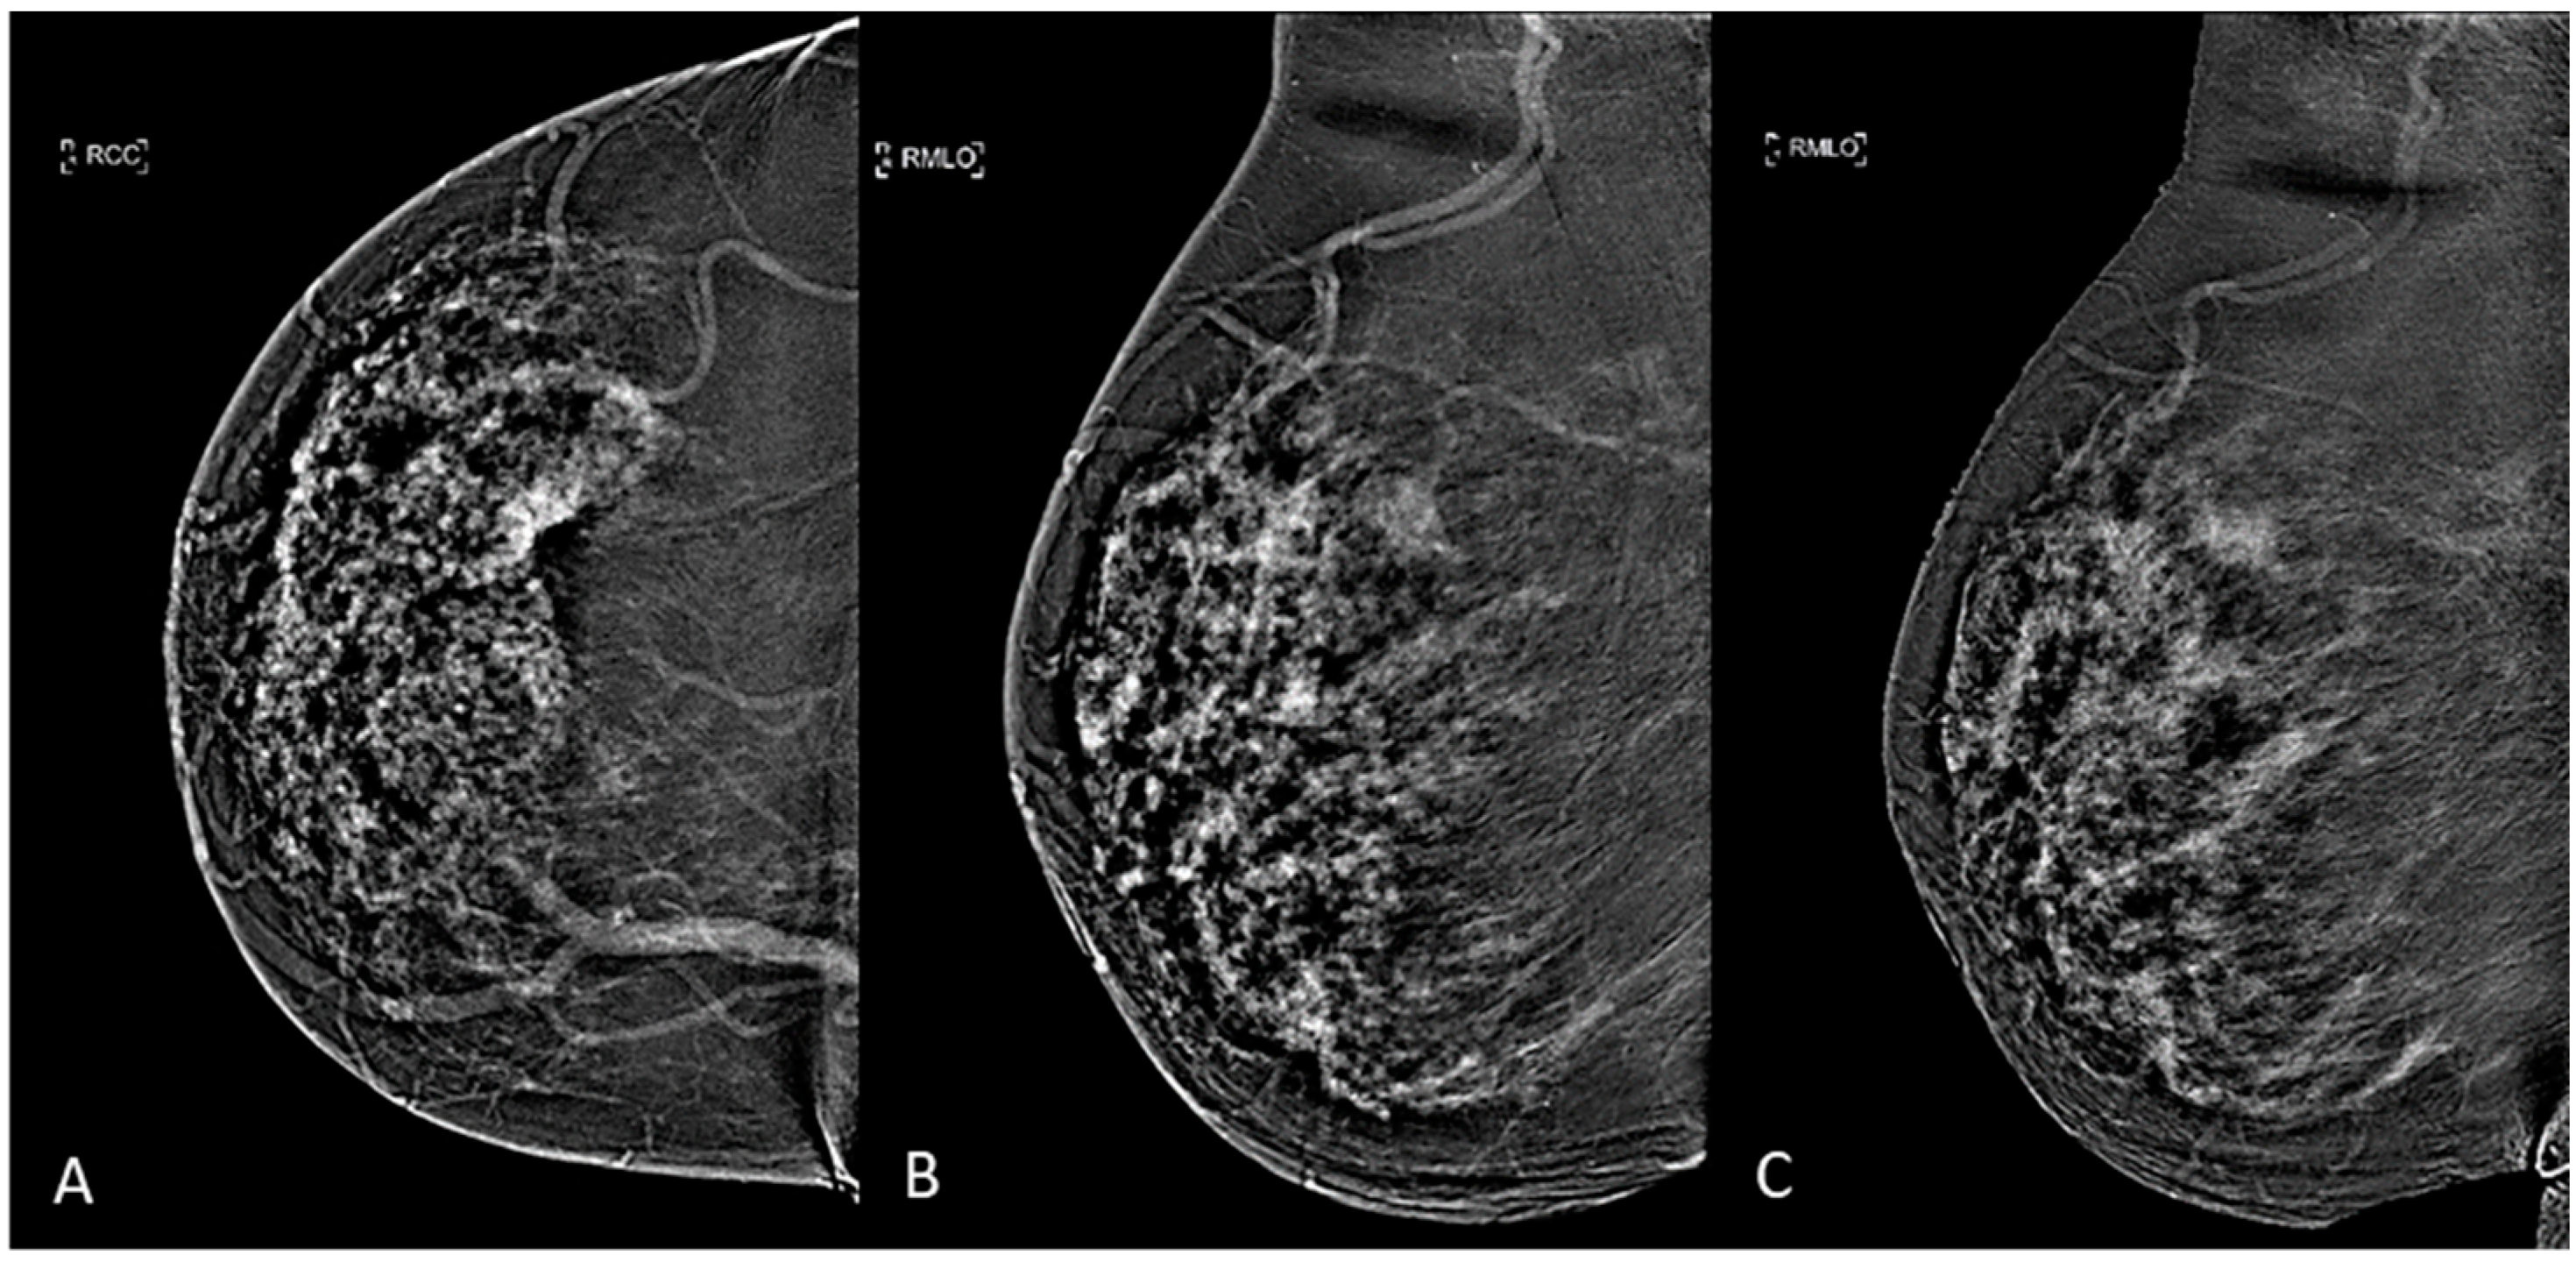

The two previously acquired images are then digitally subtracted of each other to produce a resultant recombined image that highlights contrast enhancement uptake area and gives functional information [10], as it can be seen in Figure 1. Four and eight minutes after contrast agent administration, each breast were compressed in the MLO view: early-MLO and late-MLO view images were respectively acquired (Figure 1).

Figure 1.

CEM subtracted images of a multifocal IDC in a 53-years-old woman with dense breast: (A) CC view, (B) early-MLO view, (C) late-MLO view.